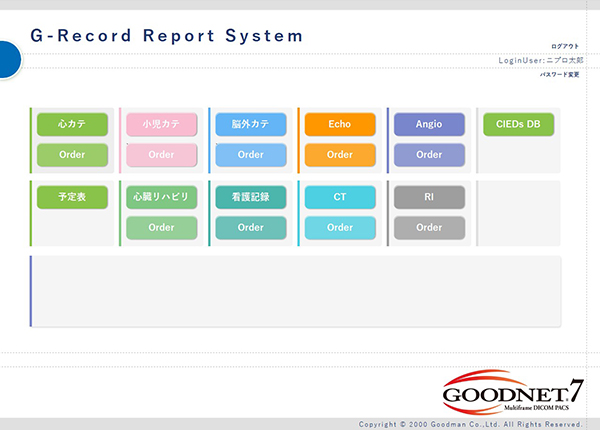

・レポートシステム「G-Record」

Goodnetや院内システムと連携することで検査情報を総合的に管理できる検査管理データベースを提供いたします。新たに遠隔モニタリング自動取込みシステム「REVOLVER」とも連携可能になりました。

各種検査情報取り込みによる誤入力防止や入力時間短縮などレポート入力支援機能にとどまらず,蓄積したデータをいかに活用できるかまで,インターベンショナルデバイスメーカーとしてのノウハウと豊富な実績,経験を活かし自社の専任スタッフが快適な医療環境作りをサポートします。DWHとの連携による患者プロファイルや採血データの取得をはじめ,各種レジストリ入力項目の対応,検査予定表,看護台帳,エコー台帳,バーコードリーダーによる使用物品の入力補助機能の提供実績も多数ございます。